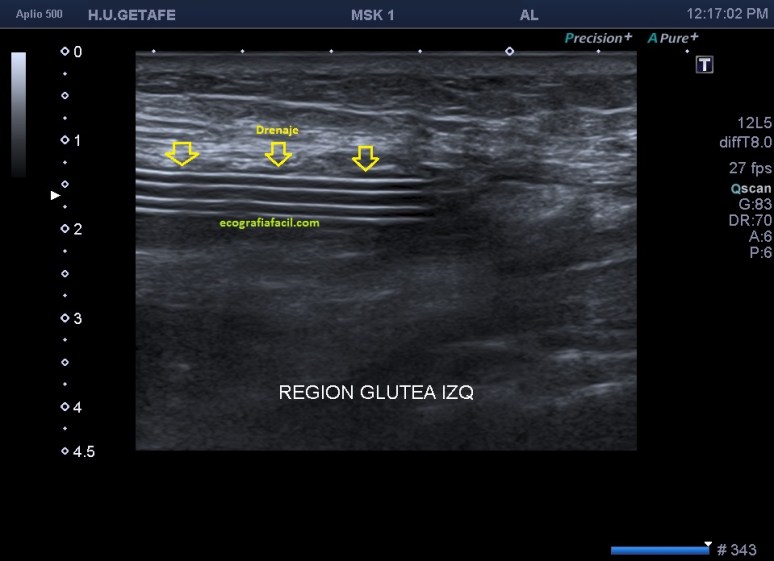

Es lo que ves en este otro caso, imagen 4, 5 y 6, donde se observan estos cambios que has visto en la primera parte de Post, pero además, aquí el caso es diferente, la etiología es distinta y en este caso, la paciente presentaba cambios en partes blandas y un gran absceso infeccioso en profundidad que requirió colocación de un drenaje.

El absceso presenta aspecto anecoico-hipoecogénico en profundidad, podemos verlos de tamaños distintos, este era grande y puedes ver en la imagen 6, como hay dos imágenes tubulares, hiperecogénicas con aspecto de cuerpo extraño que llegan hasta la colección líquida infectada comentada, mira:

6